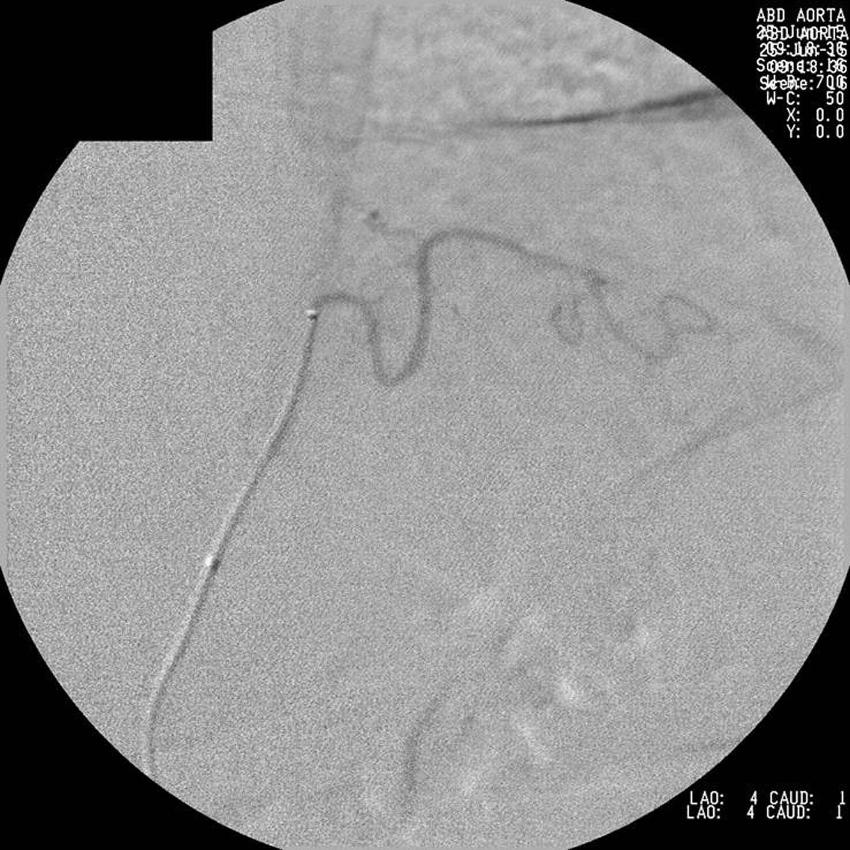

Figure 4. Left gastric artery after gastric artery embolization.

High-res (TIF) version

Figure 5. Left gastric artery after gastric artery embolization.